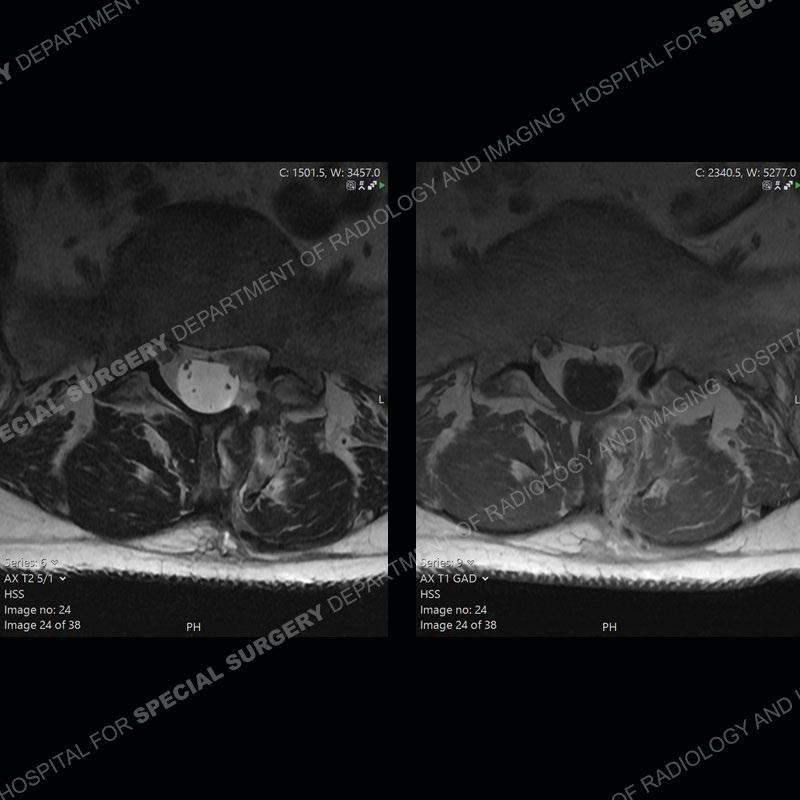

Post operative changes are seen on the left side at L5-S1 where there is near complete removal of the left sided L5 lamina, partial resection of the left L5-S1 facet joint, and resection of the left sided ligamentum flavum. In the anterolateral epidural space about the subarticular recess is a mass that demonstrates similar T1 and T2 signal characteristics to the adjacent degenerated disc. There is enhancement about the periphery of the mass, but the majority of this somewhat geographic or polyploid mass demonstrates no enhancement. The mass exerts prominent mass effect on the left S1 axillary sleeve/proximal nerve root. The left S1 nerve root shows enlargement and increased enhancement as compared to the contralateral right side.

Diagnosis: Recurrent Disc Herniation

Not as much of a diagnostic dilemma as some other cases but more so just a very nice example of what can be a difficult assessment at times. The evaluation of granulation tissue/scar/epidural fibrosis vs. disc herniation particularly in the earlier post operative period can be very difficult. Clues that can assist in identifying a disc herniation are a more geographic or polypoid nature to the mass, signal characteristics similar to the adjacent degenerated disc, mass effect upon the thecal sac/adjacent neural structures, and a typical enhancement pattern. As the disc material is avascular, as long as imaging is performed in a relatively rapid fashion after contrast administration (within 20-30 minutes), the granulation tissue around the disc will enhance but the disc material itself will not. If there is a marked delay between contrast administration and imaging, there may be diffusion of contrast into the disc making the assessment very difficult. The marked utility of contrast to help delineate disc vs. scar has led to our institution employing contrast fairly uniformly within the first two years following surgery.